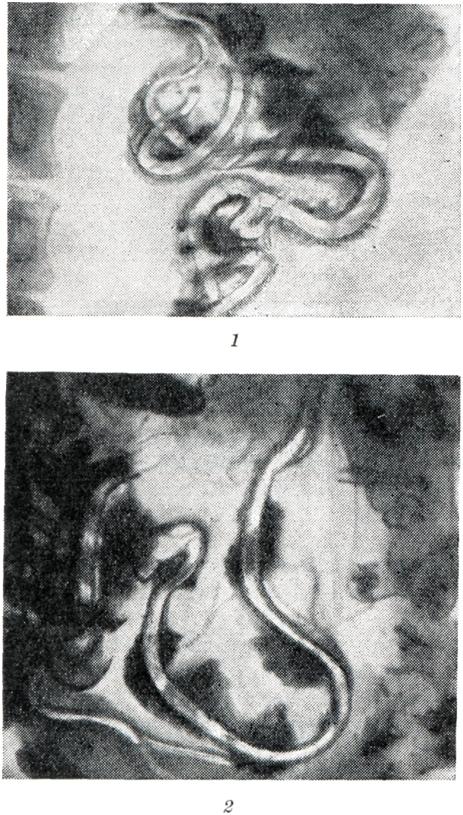

Рентгено диагностика аскаридоза имеет значение при неясных клинических проявлениях заболевания и отрицательных копрологических данных, в частности при наличии в кишечнике одних только мужских особей паразита, а также для контроля за результатами дегельминтизации. При этом используют обычную для исследования тонкой кишки методику с приемом внутрь бариевой взвеси. В процессе исследования осуществляют динамическое наблюдение за пассажем бария по тонкой кишке с выполнением обзорных и прицельных снимков. Для более тщательного и быстрого изучения тонкой кишки на всем протяжении по поводу предполагаемого аскаридоза ее заполняют взвесью бария через зонд, предварительно введенный в верхнюю петлю тощей кишки.

Рис. 8. | ||

При наличии аскарид на фоне бария в просвете тонкой кишки видны характерные лентовидные просветления, обусловленные паразитами (рис. 8, 1 и 2). Контуры этих просветлений четкие, концы — заостренные. Иногда в середине лентовидного просветления определяется узкая продольная полоска бария, находящегося в пищеварительной трубке аскариды. Под влиянием компрессии или пальпации аскариды легко смещаются, нередко начинают двигаться, меняя свое положение в просвете кишки. Одиночные аскариды чаще обнаруживаются в средних и дистальных петлях тощей кишки, а также в подвздошной. В местах максимального скопления аскариды иногда укладываются рядами параллельно друг другу. При большом количестве паразитов они могут обнаруживаться на протяжении всей тонкой кишки, а иногда — в двенадцатиперстной, толстой, в желудке и даже в желчных путях. Аскаридоз обычно сопровождается местной дистопией и дискинезией кишечника, степень выраженности которых зависит во многом от длительности заболевания, числа и размеров аскарид. При этом отчетливо выражено замедление пассажа бария, стойкие спазмы кишки, метеоризм, а также перестройка рельефа слизистой оболочки (утолщение или уплощение складок) на уровне расположения аскарид. При множественном и длительно существующем аскаридозе функциональные расстройства распространяются на весь пищеварительный тракт.